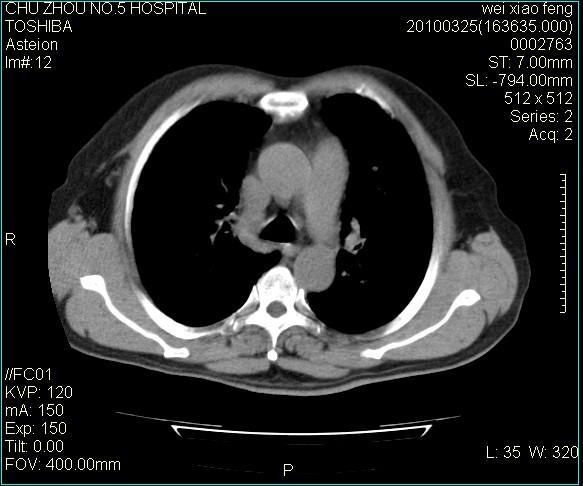

男,60岁,反复咳、痰、喘3月,加重3天。

双肺间质性改变。

间质性肺炎伴间质纤维化!不排除伴有职业病!

双肺间质纤维化,双肺血型潘散肺结核。

心功能怎么样?感觉象肺淤血。

考虑间质性肺炎伴间质纤维化。

右肺中叶结节影为原发灶,考虑右肺中叶周围型肺癌并淋巴道转移